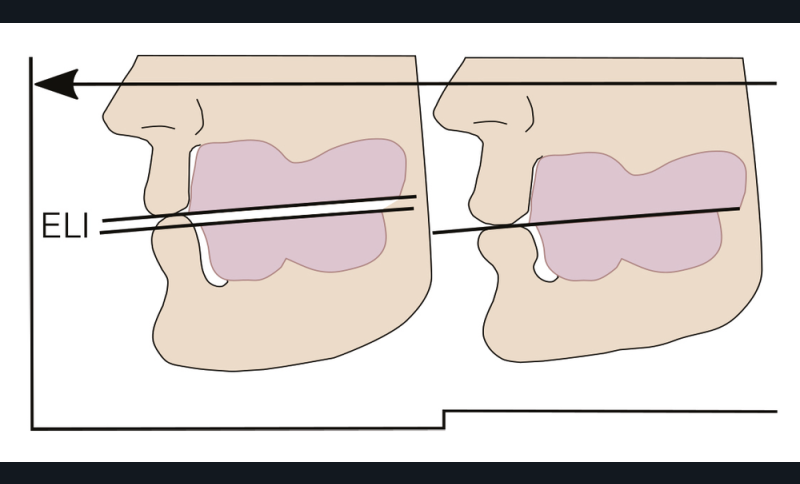

On peut aussi se servir de la déglutition pour valider le choix de la DVO. Si elle est surestimée, le patient aura tendance à se pencher en avant pour déglutir ; en cas de sous-évaluation le patient aura tendance à interposer sa langue entre les deux arcades préfigurées (fig. 22) [8].